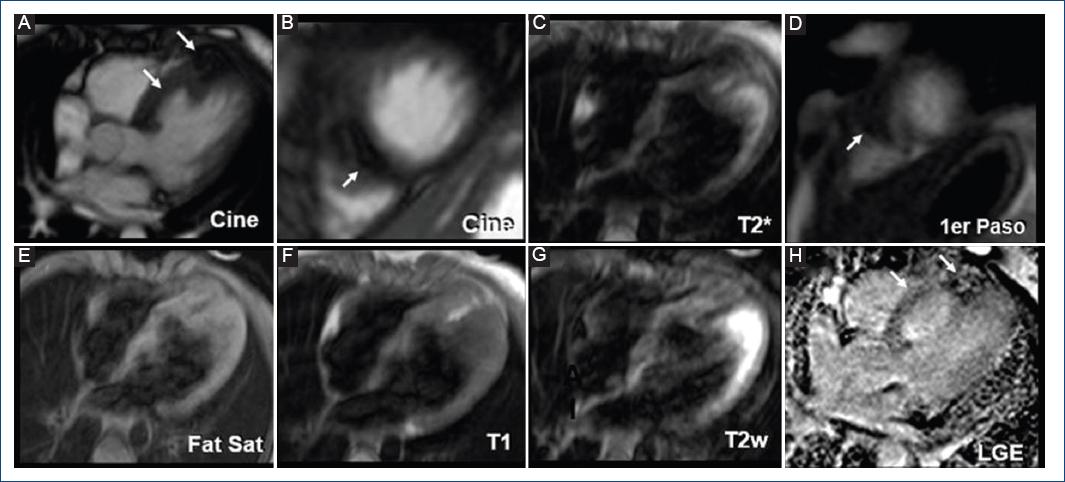

En la RM el tumor se muestra isointenso en T1 e hiperintenso en T2, comparado con el miocardio y no realza con contraste, lo que permite distinguirlo del fibroma cuando es intramural. En la TCMD el tumor es hipodenso comparado al miocardio aun posterior al contraste11,12 (Fig. 5). A pesar de tener una mejor caracterización con la RM, preferimos y recomendamos el uso de la ecocardiografía debido a que la RM requiere sedación profunda que puede descompensar a un paciente crítico y su uso lo limitamos a pacientes en que el beneficio que se obtiene es mayor al riesgo en que se somete al paciente.

Figura 5 A: imagen de resonancia magnética en cine 4C de paciente de sexo masculino de 10 años de edad con aneurisma de septum interventricular en tercio medio hacia ventrículo derecho y tumor intramiocárdico en septum interventricular tercio apical. B: cine dos cámaras con tumoración intramural (9 x 6 mm) septal apical. C: T2* hipointensa. D: primer paso tumoración hipointensa intramural. E: T1 FatSat hipointensa. F: T1 hiperintensa. G: T2 W isointensa. H: imagen en realce tardío de gadolinio, hipertensa, reforzamiento tardío intramiocárdico lineal en la pared del aneurisma.